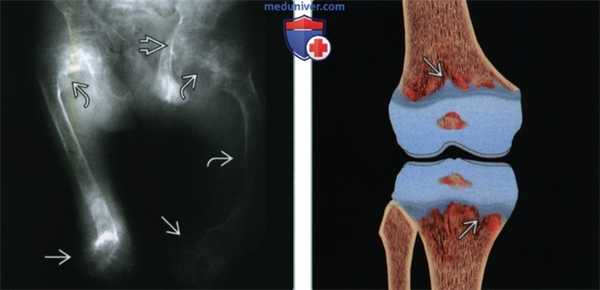

(Слева) Рентгенография в ПЗ проекции: визуализируются обе бедренные кости у ребенка с тяжелой формой гипофосфатазии. Имеются выраженные изменения пластинок роста (расширение и неровность контуров). Остеомаляция осложнилась угловыми деформациями в проксимальных отделах обеих бедренных костей, а также в диафизе левой бедренной кости. Имеются протрузионные деформации тазобедренных суставов, характерные для остеомаляции.

(Справа) На рисунке во фронтальной плоскости показана гипофосфатазия, характеризующаяся выраженной неровностью контуров пластинок роста и отростками суставных хрящей, распространяющимися в метафизы.